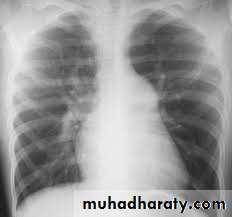

2-X-ray Studies

Cardiomegaly with enlargement of the RA and right ventricle (RV) may be present.

A prominent pulmonary artery (PA) segment and increased pulmonary vascular markings are seen when the shunt is significant